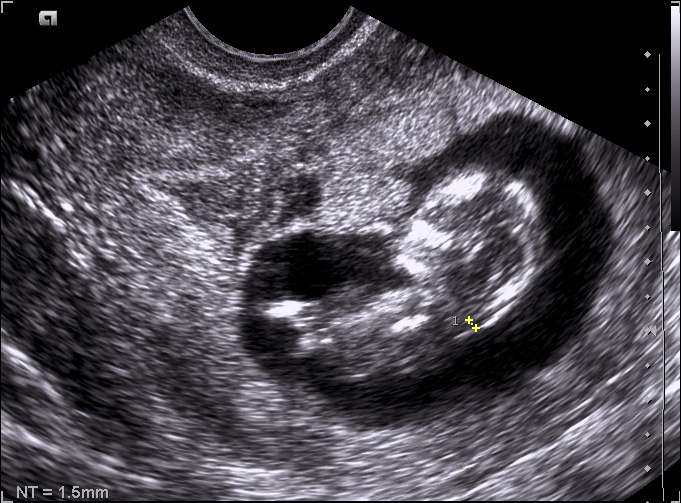

Optymalny wiek ciążowy dla pierwszego badania prenatalnego zawiera się między 11-13+6 tygodniem ciąży, długość ciemieniowo-siedzeniowa (CRL) musi się mieścić między 45 a 84 mm. Poza stwierdzeniem ciąży żywej, można określić jej dokładny wiek, stwierdzenie obecności dużych wad płodu, a w ciąży mnogiej ocena ilości płodów, kosmówkowości.

Dodatkowo ocena i pomiar markerów I trymestru pozwala na ocenę ryzyka aberracji chromosomalnych.

Do markerów tych należy: przezierność karkowa, kość nosowa, przepływ w przewodzie żylnym, zastawka trójdzielna, kąt szczękowo - twarzowy.